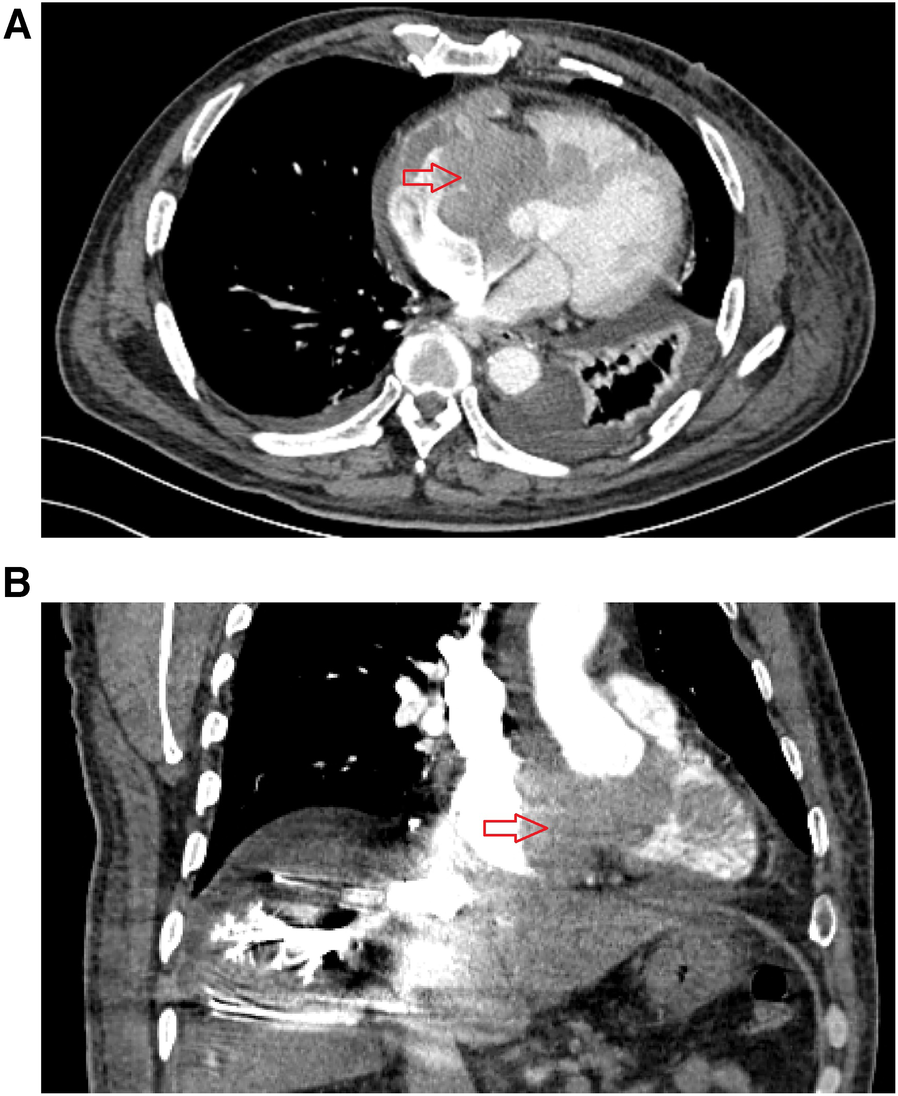

A 64 year-old man was admitted to our hospital on September 2, 2022, owing to symptoms of a tachycardia and shortness of breath. Physical examination at admission revealed the following: body temperature: 36.5°C, heart rate: 51 times/min, pulse: 51 beats/min; blood pressure: 102/68 mmHg, poor spirit, edema of the trunk, yellow sclera, slight cyanosis of the lip, no filling of the jugular vein, coarse breath sounds in both lungs, no enlargement of the heart boundary, arrhythmia, soft abdomen, and severe pitting edema of the lower limbs. Moreover, laboratory tests revealed the following: cardiac troponin I (cTNI) < 0.02 ng/ml (normal range: <0.53 ng/ml), creatinine-kinase-MB: 5.49 ng/ml (normal range: <5.0 ng/ml), myohemoglobin: 216.82 ng/ml (normal range: <110 ng/ml), D-dimer: 1214.27 ng/ml (normal range: <200 ng/ml), and B-type natriuretic peptide: 2460.72 pg/ml (normal range: <100 pg/ml). Electrocardiography indicated sinus rhythm, third-degree atrioventricular block, full-lead low voltage, QT interval prolongation, and borderline escape rhythm. Echocardiography revealed a hypoechoic mass extending from the right atrium to the right ventricle and obstructing the forward flow of the tricuspid valve. The size of the mass was approximately 66 × 40 mm (Figure 1). Computed tomography revealed the following: (1) irregular shape of the right heart, with the enhanced right auricle, right atrium, and ventricle exhibiting irregular clusters and relatively weakly enhanced areas. The CT value after enhancement was approximately 70–90 HU, while the larger cross-section was approximately 6.2 × 6.9 cm. The local boundaries between the lesion, pericardium, and left atrium were unclear, while the ventricular septum was irregular and thickened; (2) the filling of the superior vena cava and left and right brachiocephalic veins was not uniform; (3) the pulmonary artery and its branches in the upper, middle, and lower lobes of the right lung were poorly developed, while the local lumen was suspected to be uneven, exhibiting a few patchy and slightly low-density shadows. A suspicious low density shadow was observed at the edge of the upper and lower pulmonary arteries of the left lung; (4) the two lungs were dispersed with flaky shadows of increased density, the volume of the lower lobe of the left lung was reduced, a dense shadow was present in some lung tissues, and the enhancement was visible; (5) the bronchial segment of the left inferior lobe of the lung was slightly narrowed, while part of the bronchus of the left inferior lobe was unclear; (6) pericardial effusion, bilateral pleural effusion, left interlobar fissure, and adjacent lung hypoinflation; (7) the thoracic section of the esophageal wall was slightly thickened, approximately 0.4 cm; (8) swelling of left axilla, chest wall, and back soft tissue; (9) abdominal fluid, the local adipose space in the abdominal area was seen as lamellar and slightly high-density shadows; (10) multiple small veins in inferior vena cava and right lobe of liver were developed in advance; and (11) the adipose space in the abdominal cavity was blurred, with multiple pieces being increasingly flocculent, while the fascia around both kidneys was thickened (Figure 2).

Figure 2

Preoperative enhanced computed tomography results for patient in September 2, 2022. (A) The cross-sectional image shows a mass in the right atrium, with irregular patchy enhancement in the right atrial appendage, right atrium, and right ventricular region, with a CT value of approximately 89 Hounsfield units. The interventricular septum is irregularly thickened. (B) Coronal view shows a mass in the right atrium, uneven opacification in some areas of the superior vena cava, delayed opacification of the inferior vena cava and veins in the right lobe of the liver.